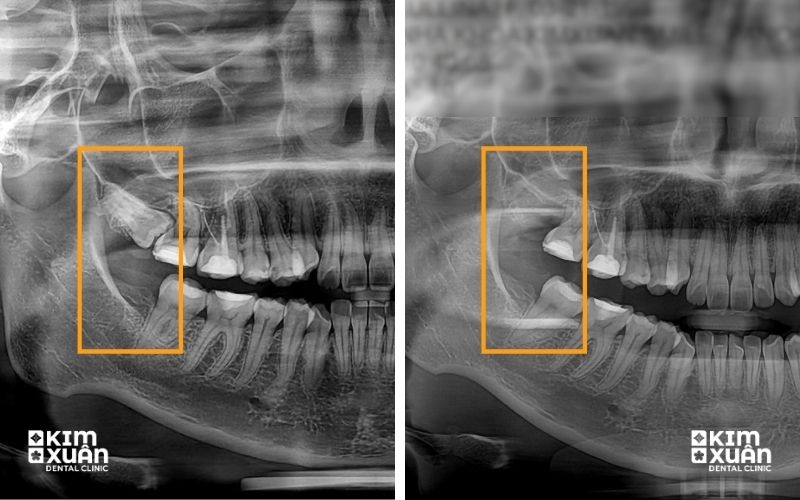

Thăm khám tổng quát và chụp phim X-quang trước khi nhổ

Bác sĩ trực tiếp đánh giá vị trí răng, mức độ khó và nguy cơ liên quan

Lưu ý: Răng khôn mọc càng phức tạp thì thời gian nhổ, kỹ thuật can thiệp và trang thiết bị hỗ trợ càng nhiều. Những trường hợp răng mọc lệch nặng hoặc mọc ngầm sâu thường cần tiểu phẫu, bóc tách mô và chia thân răng, vì vậy chi phí nhổ răng khôn sẽ cao hơn so với răng mọc thẳng. Để biết chính xác mức giá, người bệnh cần được bác sĩ thăm khám và chụp phim X-quang đánh giá vị trí răng.

Răng khôn mọc thẳng thường dễ nhổ, ít xâm lấn nên chi phí thấp. Ngược lại, răng khôn mọc lệch, mọc ngang (45 - 90 độ) hoặc mọc ngầm trong xương hàm sẽ khó can thiệp hơn, cần bóc tách mô và chia thân răng, do đó chi phí nhổ răng khôn cao hơn.

Với răng khôn mọc ngầm hoặc mọc khó, bác sĩ thường chỉ định tiểu phẫu để đảm bảo an toàn, tránh ảnh hưởng đến dây thần kinh hàm dưới và hạn chế biến chứng sau nhổ.